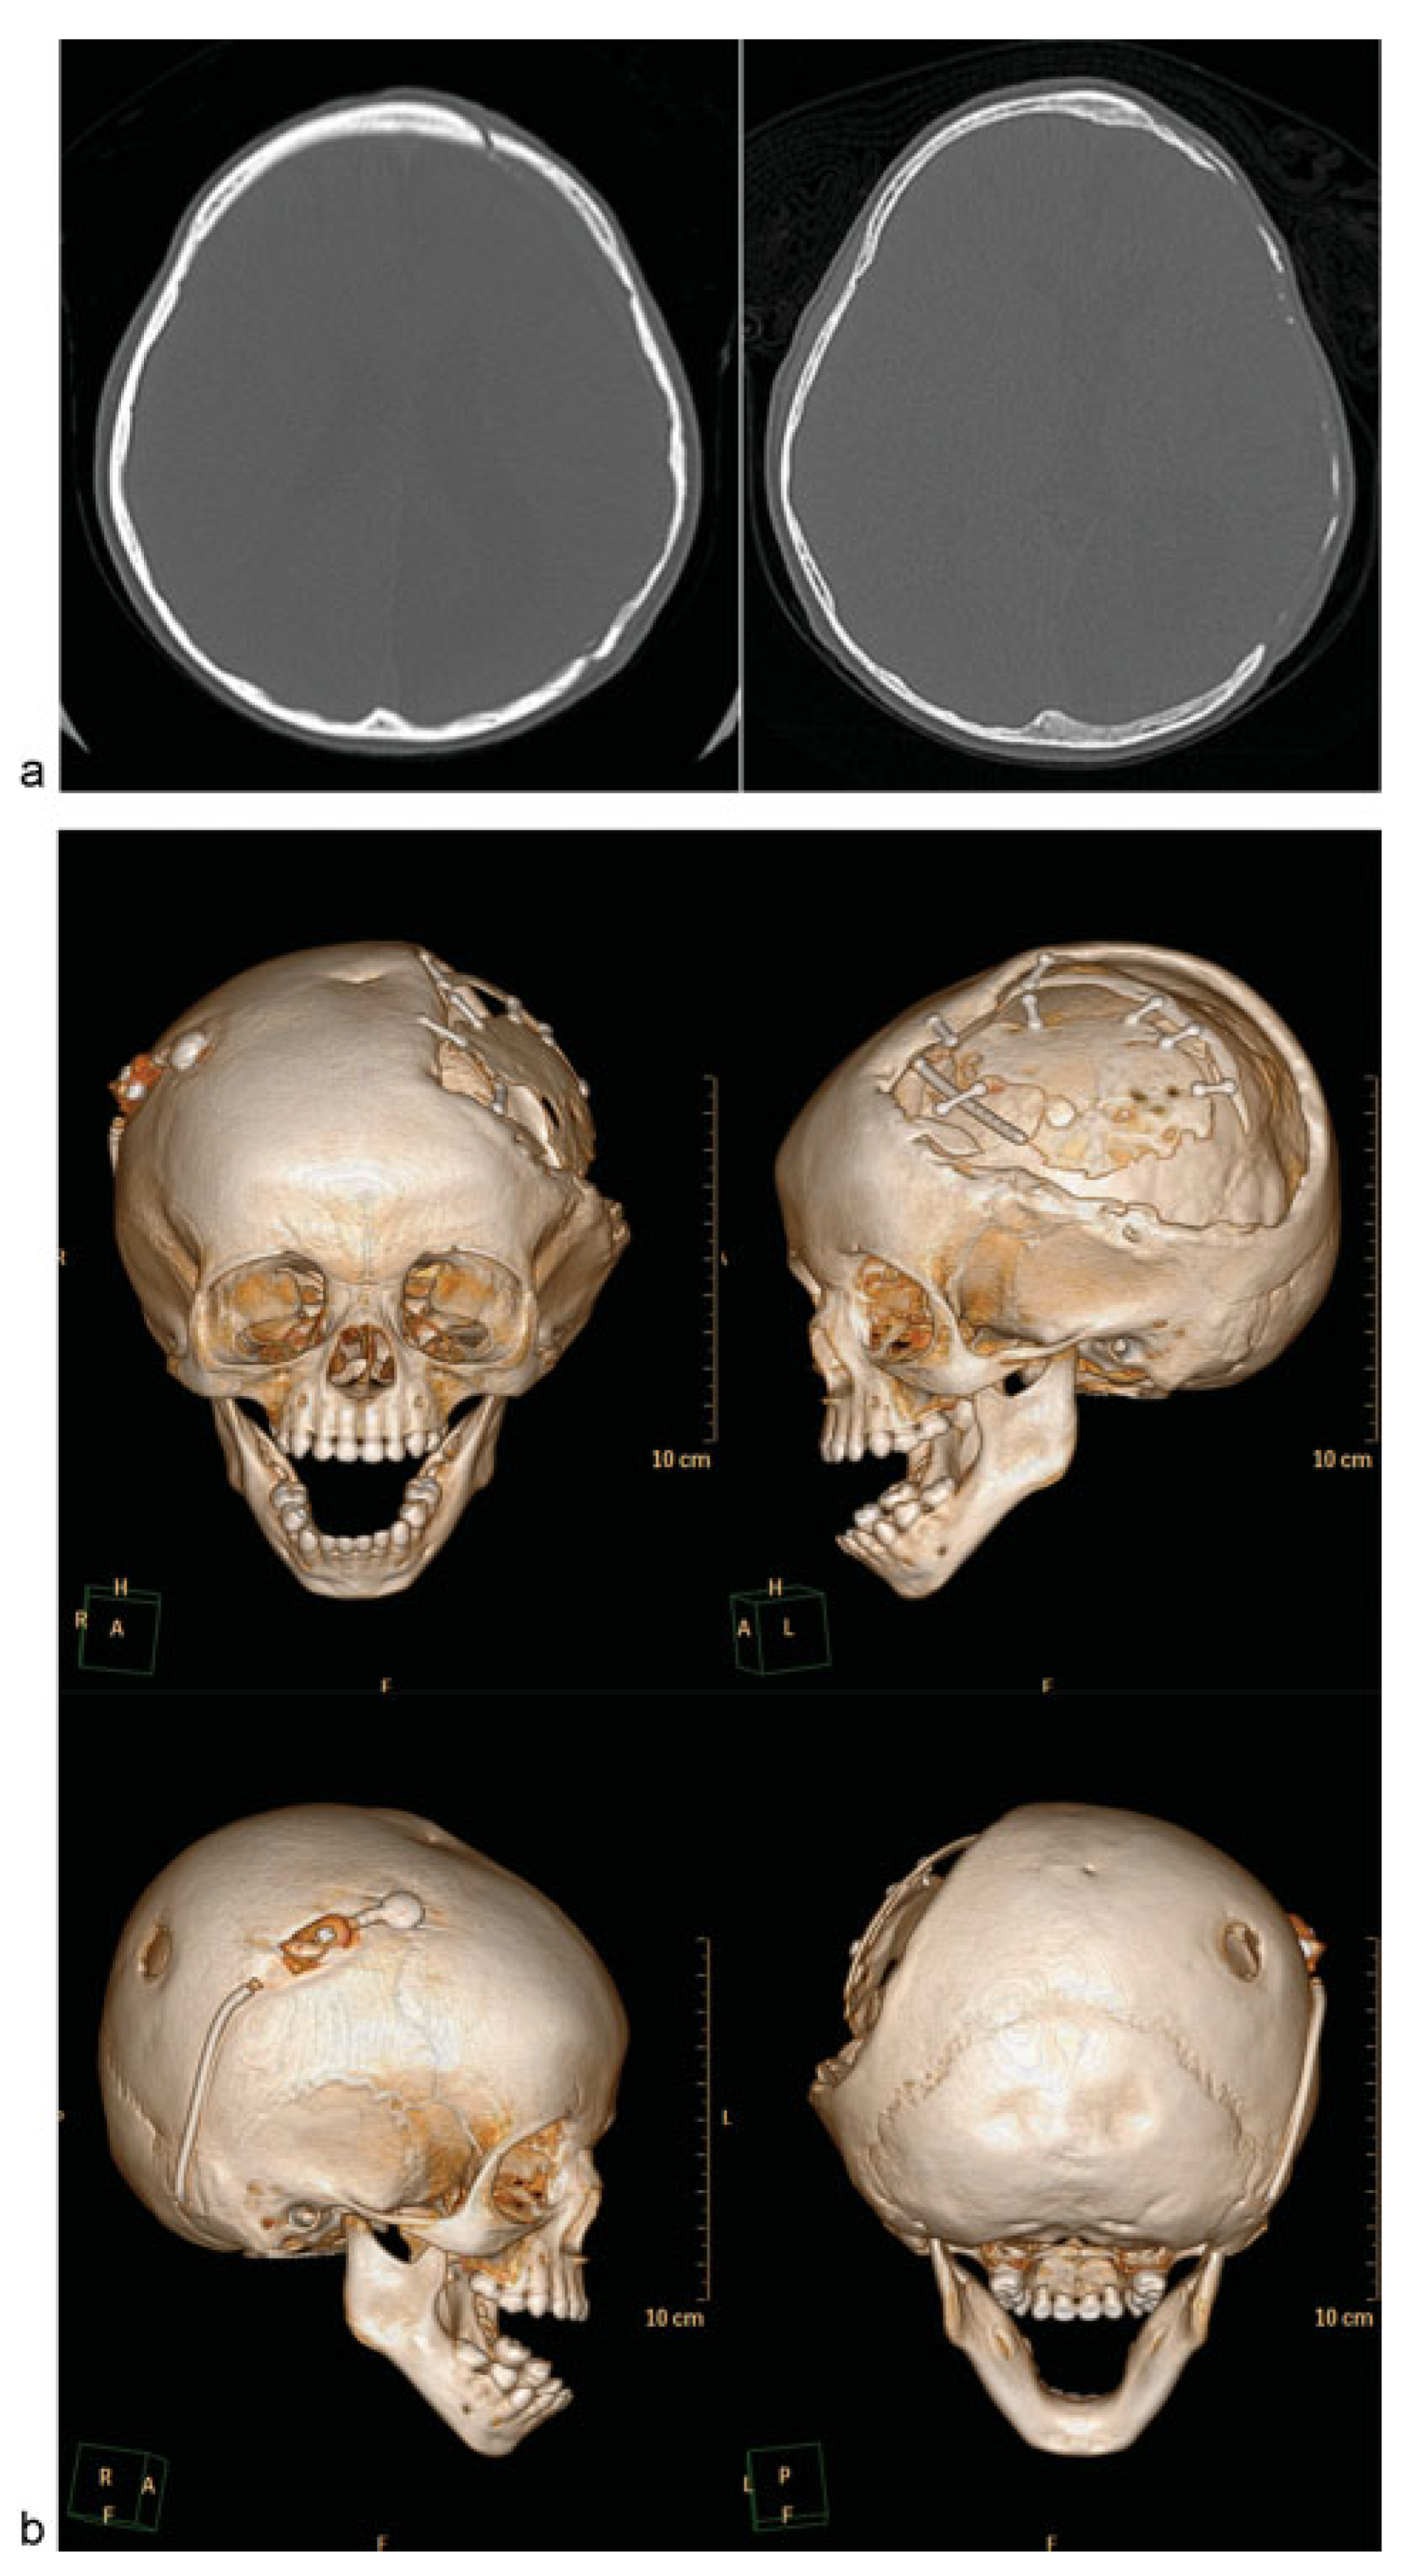

Autologous cranioplasty after decompressive craniectomy is considered the gold standard in pediatric care because of the ability of the bone graft to reincorporate into the skull (osseointegration), lower risk of material rejection, and ability to allow growth of the skull. There are several approaches to this form of reconstruction (Table 2). The three main ways to perform an autologous cranioplasty use bone stored in the body, cryopreserved bone, or bone flaps harvested from a donor site. With pediatric patients, additional considerations must account for the high incidence of bone resorption (Figure 1a–c), the immature osseous skeleton, and future growth.

Figure 1.

Case 1: An 18-month-old child with history of decompressive craniectomy for acute traumatic subdural hematoma, with at right frontal ventriculoperitoneal shunt in place for posttraumatic hydrocephalus. The autologous bone flap was retrieved from bone freezer storage and replaced 3 months after the initial trauma to repair the large left frontoparietotemporal skull defect. The autologous cranioplasty failed with bone flap resorption noted 6 weeks later, which was near complete by 4 months after autologous cranioplasty. An exchange cranioplasty was done, with re-siting of the ventriculoperitoneal shunt to the left occipital approach to avoid the bilateral cranioplasty areas. (a) Axial head computed tomographic (CT) scan immediately after autologous cranioplasty (left); axial CT scan of the same patient with bone flap resorption 4 months later (right). (b) Three-dimensional (3D) CT reconstructions showing bone flap resorption and right frontal ventriculoperitoneal shunt in place. (c) Axial CT scan (left) with corresponding intraoperative skull defect (right) at time of second reconstruction (exchange cranioplasty) after bone flap resorption. (d) Exchange cranioplasty. Measuring the donor site for the exchange and templating the cranial defect. (e) Exchange cranioplasty in process after placement of the freshly harvested contralateral bone graft. (f) Harvesting autologous particulates for bone grafting from the inner surface of a full-thickness calvarial flap. (g) Bilaminate mesh cranioplasty: inner layer of mesh in the right frontoparietotemporal calvarial defect, forming the epidural inner cortex. (h) Exchange cranioplasty completed with the recreated “diploic space” in between mesh layers filled autologous particulate bone mixed with demineralized bone matrix and autologous blood, then covered with the outer layer of mesh. (i) 3D CT scan 3 months after exchange cranioplasty showing partial consolidation of particulate graft on the left, incorporation of the full-thickness calvarial graft on the right with good skull contour. The shunt was re-sited to avoid the cranioplasty areas. (j) Axial CTscan 3 months after exchange cranioplasty.

When bone is needed to provide cranial coverage, there are several options if the removed bone is no longer available because of trauma, loss, or infection. These options from the cranium include full-thickness grafts, split-thickness grafts, and particulate bone grafts. These three reconstructive approaches all involve using bone from the healthy parts of the skull to repair the defect and have been shown to have a lower rate of resorption than grafts from elsewhere on the body.[22] Full-thickness calvarial grafts are often used when there is concern about healing, such as, in the cases of the previous failed reconstruction. This approach provides good coverage of the cranial defect but creates a donor site to be repaired. This type of defect can be done using an exchange cranioplasty (Figure 1d, e), in which the existing defect is repaired with the full-thickness calvarial graft, and the donor site is repaired with particulate bone graft harvested from the full-thickness graft. Rogers et al reviewed 20 cases, and found that 15 of 20 had complete healing, and the size of the defects decreased by an average of 96%. This exchange cranioplasty method, although it involves an additional operative site, has been found to be highly effective even for large cranial defects as children have high-osteogenic potential.[23]

Particulate grafts can also be used to repair defects directly. In young children, the supply of autologous bone is limited; particulate grafts can be advantageous as they can be harvested with minimal morbidity (Figure 1f).[24]

Bilaminate constructs with particulate grafts can be made by placing bioresorbable mesh endocranially on the dura, laying in bone particulates mixed with blood, demineralized bone matrix paste and other bone growth enhancing agents, and buttressing with an outer layer of bioresorbable mesh. (Figure 1g, h) This method has been used successfully to augment small and large defects. Chao et al report that all the 11 patients in their initial experience achieved clinically stable reconstructions.[25] This method has the benefit that the donor site returns to full thickness over time. It is best used when the reconstructive site has good healing potential and unscarred dura. Alternatively, an exchange cranioplasty or other reconstructive method may be indicated.[23,26] (Figure 1i, j).